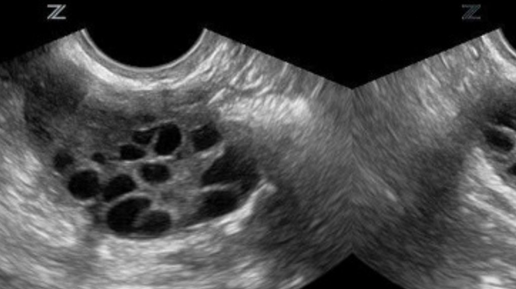

Слышали про такое? Ставьте сердечко и поехали. Мультфиолликулярные яичники – это не диагноз. Это всего лишь ультразвуковое заключение, которое может означать наличие заболевания, а может ни о чем не говорить и быть случайной находкой. Когда можно говорить о наличии мультифолликулярных яичниках? Если в структуре яичника определяется 12 и более (по критериям некоторых медицинских сообществ 20 и более) мелких фолликулов диаметром до 9 мм и/или объем яичника составляет 10 и более мл. Чтоб посчитать объем яичника нужно перемножить его ширину, длину и толщину, и полученную цифру разделить пополам...